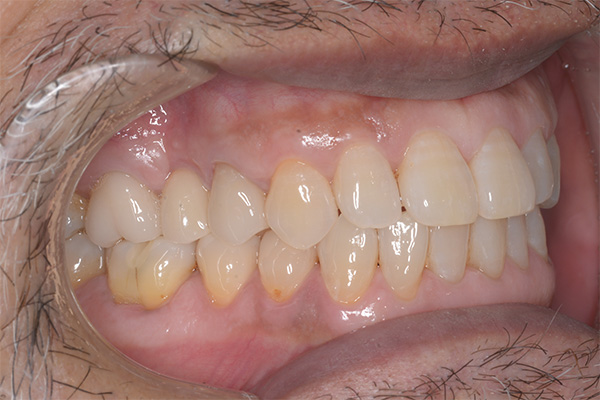

Case.03

インプラントの症例 インプラントの症例

治療前〜治療後のレントゲン写真

患者様の要望過去に治療したブリッジを外し咬み合わせの平面を整えて、被せ物や詰め物を綺麗にしたい。

治療期間10ヶ月

治療費用約1,600,000円

治療内容インプラント2本、アンカースクリューを用いた部分矯正、

セラミックによる補綴治療

治療のリスクセラミックの破折の

可能性